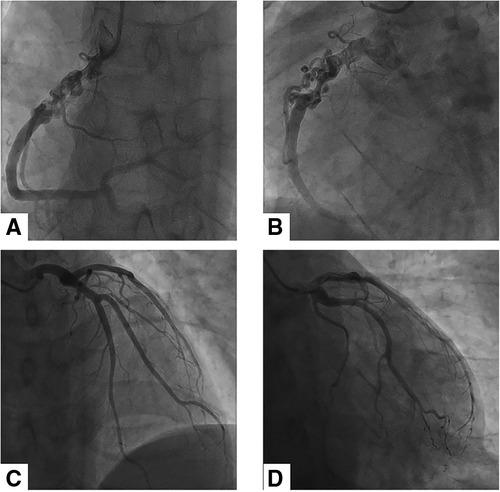

Electrocardiography showed sinus rhythm. Transthoracic echocardiography (TTE) indicated normal cardiac structure and ventricular function, with a normal ejection fraction of 65%. Computed tomography coronary angiography (CTCA) showed that there was no lumen stenosis in the left anterior descending artery or left circumflex artery (Figures 1A,B). However, a braid-like change was shown at the proximal portion of the right coronary artery (RCA). The vessel was divided into multiple small channels with a slightly distorted course along a 2 cm length of segment, subsequently, the channels merged again into a normal lumen. Patchy calcification was found in the structure (Figures 2A–D). In order to further clarify the possible etiology, the patient underwent coronary angiography (CAG), which demonstrated the same imaging findings as the CTCA (Figures 3A–D). Distal to the woven segment, the downstream blood flow was normal with a thrombolysis in myocardial infarction III (TIMI-III) grade blood flow. Unfortunately, because of the small diameter, the patient did not undergo intravascular ultrasound (IVUS) and optical coherence tomography (OCT) examination.

Figure 3. Coronary angiographic findings of the patient. (A) and (B) showed the braid-like change at the proximal portion of RCA. There was a normal blood flow in the distal segment of the anomaly. (C) and (D) revealed the normal left anterior descending artery and left circumflex artery.